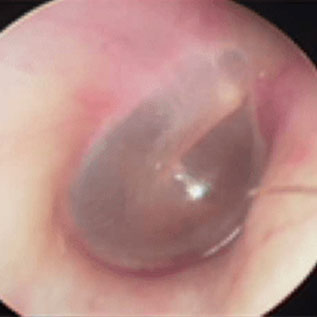

当院ではCTや内視鏡検査が可能です。

撮影した画像を用いて、わかりやすい説明を心がけます。